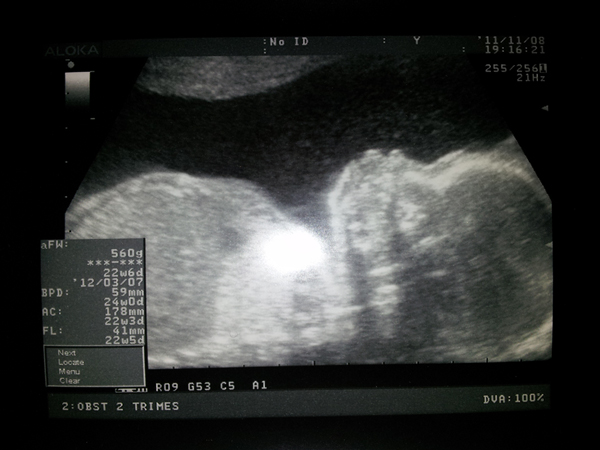

Ayer estaba el peque mucho más tranquilo, no se movía tanto como la eco anterior, de hecho estaba todo pachorrón como echándose la siesta. Pesa ya 560 gr!! maeee…

El gine nos sacó una eco genial en la que se le ve de perfil y es que se le ven unos mofletacos para comérselos… Aaains, ¡¡Qué ganitas tenemos de conocer al «pequeño» Óscar!! ^_^